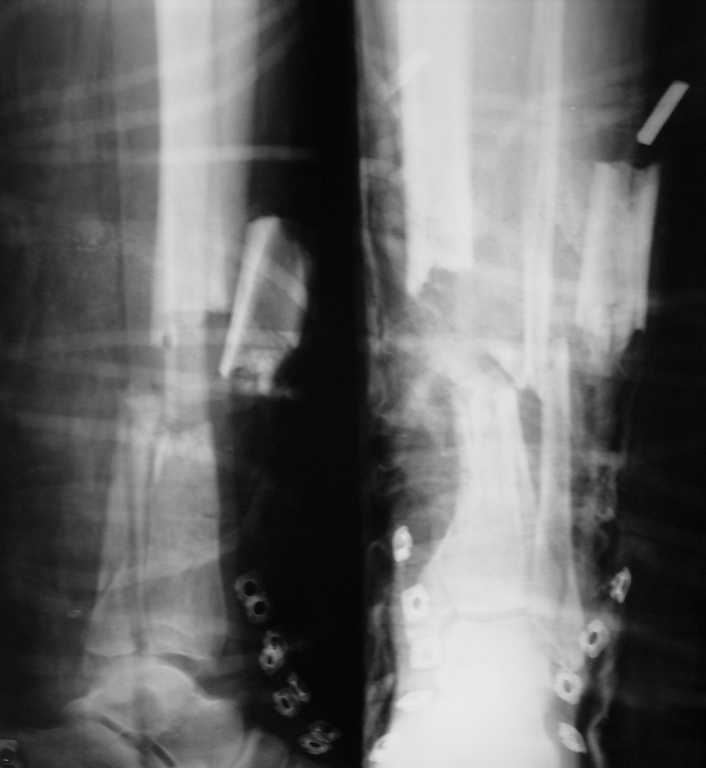

[Ortho] открытый многооскольчатый перелом костей голени

больной 38 лет, бытовая травма, доставлен через 30 мин после травмы.если можно, хотелось бы

получить рекомендации по оптимальному методу лечения данного перелома.какие будут

мнения?